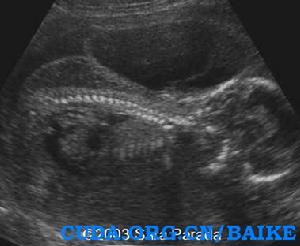

超聲發現:囊性水囊瘤是嚴重X單體的早孕和中孕期典型的徵象。妊娠晚期,孤立的胸腔積液和廣泛的水腫可以發生。最常見的心臟畸形是主動脈弓縮窄。